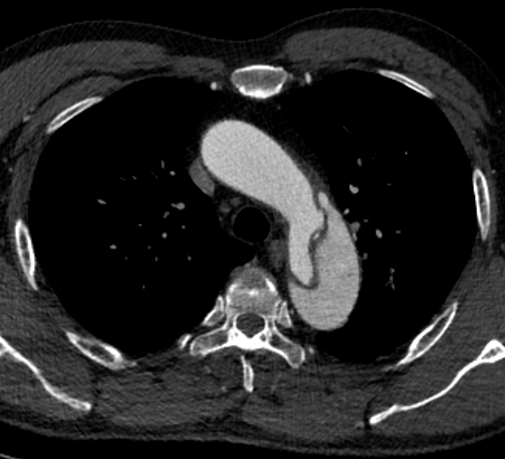

不久前的一天,北京天坛医院心脏及大血管病中心电话铃骤然响起,来电显示是急诊胸痛中心的电话:“患者背部撕裂样剧痛1小时,CTA提示主动脉夹层,请心外科紧急会诊。”正在值班的刘扬内心一紧,打开影像系统,诊断显示为急性B型主动脉夹层,这意味着患者的生命可能危在旦夕。放下电话,刘扬火速赶往急诊。

“急性主动脉夹层是死亡率非常高的疾病,A型主动脉夹层发病48小时内的死亡率在50%左右,一周后死亡率达到80%,如果主动脉突发破裂,基本没有抢救的时间和机会。B型主动脉夹层的死亡率相对较低,需保守治疗两周后介入手术治疗效果最佳,太早主动脉急性水肿未消容易出现新发破口,太晚则假腔血栓化。”徐东叮嘱,患者病情十分凶险,严格控制病情进展,如有病情变化,随时调整治疗策略。

侯先生入院以来,心脏及大血管病中心徐东主任团队为患者开始了紧张有序地治疗。前几日,团队为侯先生行“胸主动脉覆膜支架腔内隔绝术”治疗,经过团队的全力奋战,手术成功,目前侯先生恢复良好。复查结果显示主动脉夹层近端破口封堵完全,效果良好。